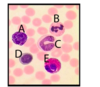

In this cross section of a peripheral nerve, what type of fibre has a morphology as illustrated by C?

- C axon

- A-beta axon

- A-gamma axon

- A-alpha axon

- A-delta axon

In this cross section of a peripheral nerve, what type of fibre has a morphology as illustrated by C?

- C axon

- A-beta axon

- A-gamma axon

- A-alpha axon

* *5. A-delta axon**